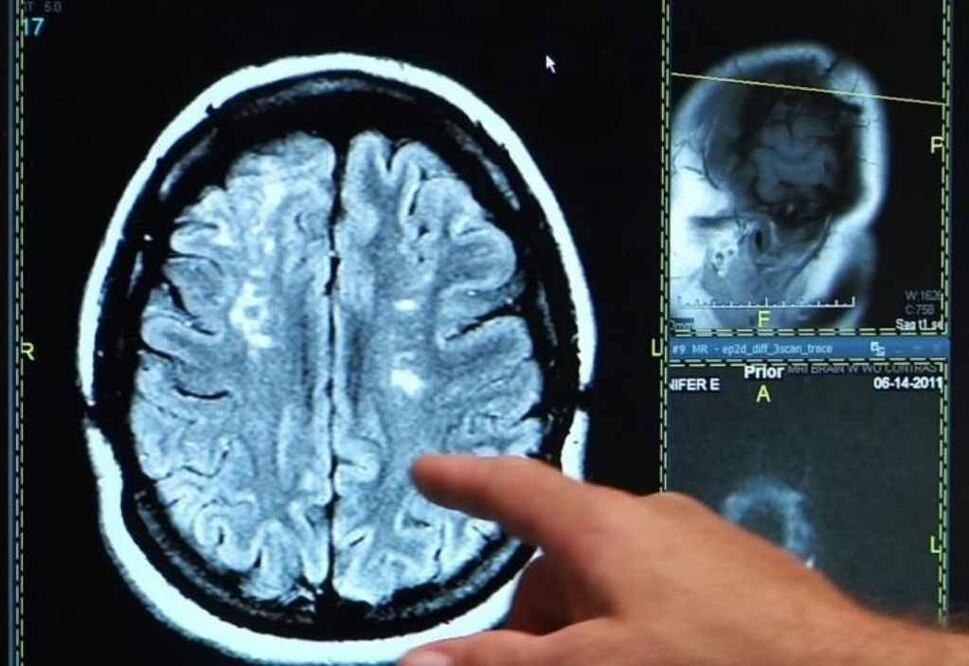

Los nacidos entre 1945 y 1954 pueden ser considerados la "generación más sana en cuanto a accidentes cerebrovasculares", según un estudio realizado por la Universidad de Rutgers, en Nueya Jersey, Estados Unidos, que encontró la incidencia más baja de ictus isquémico en este grupo de edad en los últimos 20 años.

Por el contrario, la tasa de accidente cerebrovascular es más del doble en la generación X, es decir, las personas nacidas entre 1965 y 1974, durante el mismo periodo de tiempo.

Los investigadores analizaron más de 225.000 registros de datos de accidente cerebrovascular entre 1995 y 2014, separados en cinco grupos, cada uno con una edad de 10 años. El análisis, que se publica en 'Journal of the American Heart Association', encontró que las personas nacidas en los 20 años previos a 1945 y los nacidos en los 20 años posteriores a 1954 tenían mayores riesgos de accidente cerebrovascular. Sólo el grupo que ahora está entre 60 y 70 años de edad vio una reducción en la incidencia de accidente cerebrovascular durante el intervalo de años incluidos en el estudio.